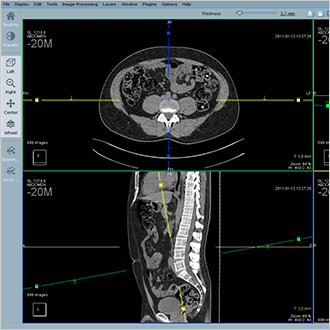

Hyper.PACS

Notre solution Hyper.PACS est un système d’archivage et de transmission d’images universel compatible avec toutes les images médicales, DICOM et non DICOM. Elle repose essentiellement sur trois piliers : la rapidité, la stabilité et la sécurité.

Hyper.PACS offre un accès rapide aux données, une stabilité et une sécurité des données à 100 %. L’interface a été développée en collaboration avec les utilisateurs pour offrir des fonctionnalités de diagnostic, de visualisation et de télémédecine intuitives.

Le flux est optimisé par les protocoles de gestion d’affichage, la consultation de l’historique et le stationnement de session. Des modules complémentaires sont disponibles pour la planification orthopédique et l’échange d’images de télémédecine.